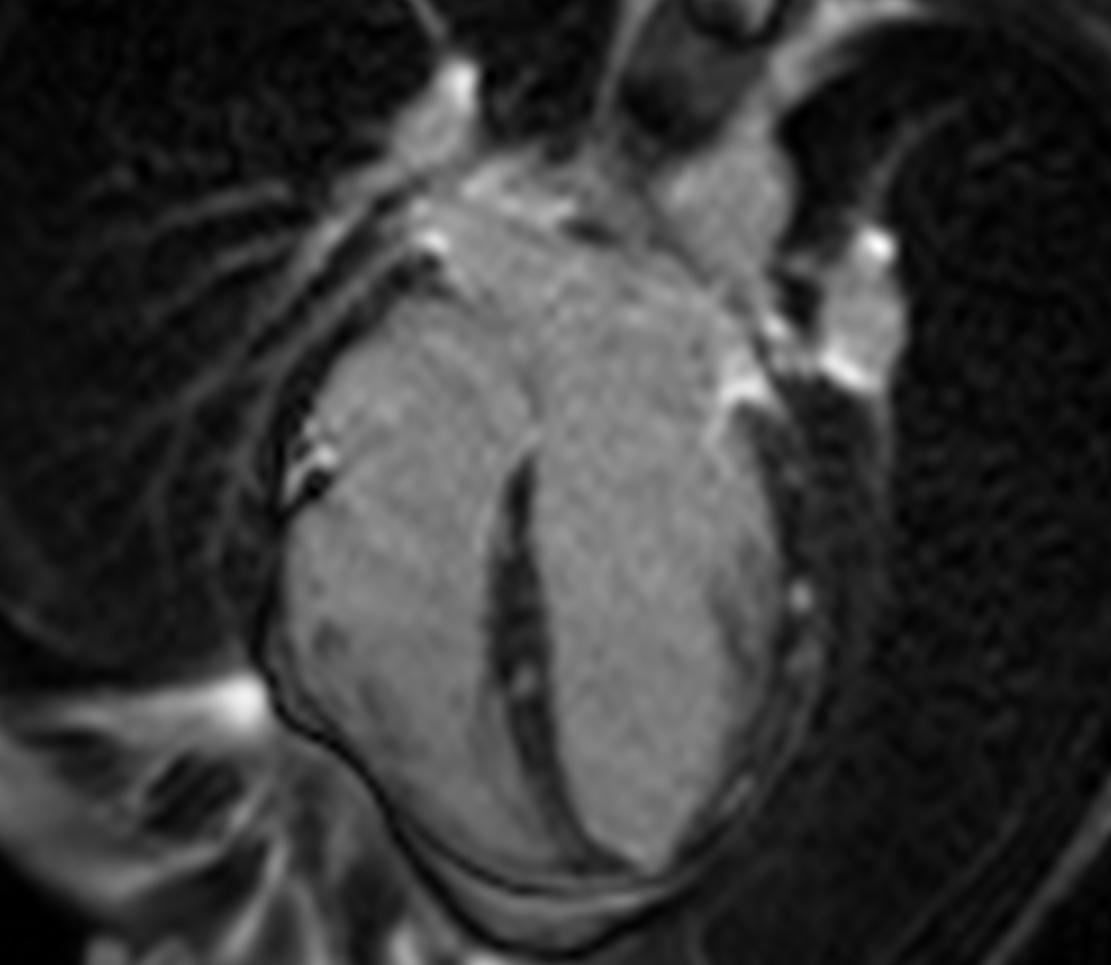

4 chamber late gadolinium enhancement